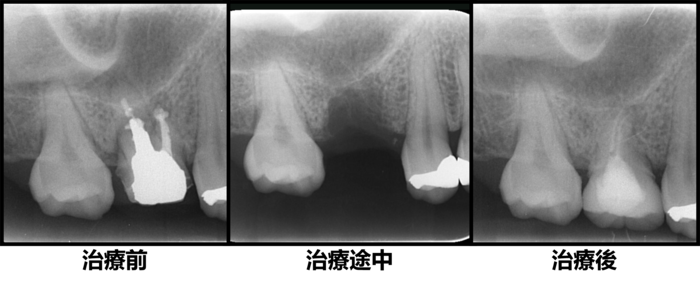

初診時デンタルX線写真

初診時デンタルX線写真とCT画像。

根管外に不透過像とそれを取り囲む透過像を認める。

コアを除去すると、分岐部へつながるパーフォレーションを認めた。

これが排膿の原因であったため、保存は困難と判断した。

移植手術3ヶ月後のレントゲン画像

移植3ヶ月後。

歯根周囲に透過像を認めるが動揺などはなく、歯周ポケットも形成されていなかった。

移植12ヶ月後のレントゲン

移植12ヶ月後。セラミッククラウンで歯冠を修復した。

デンタルX線写真では透過像もほぼ消失している。